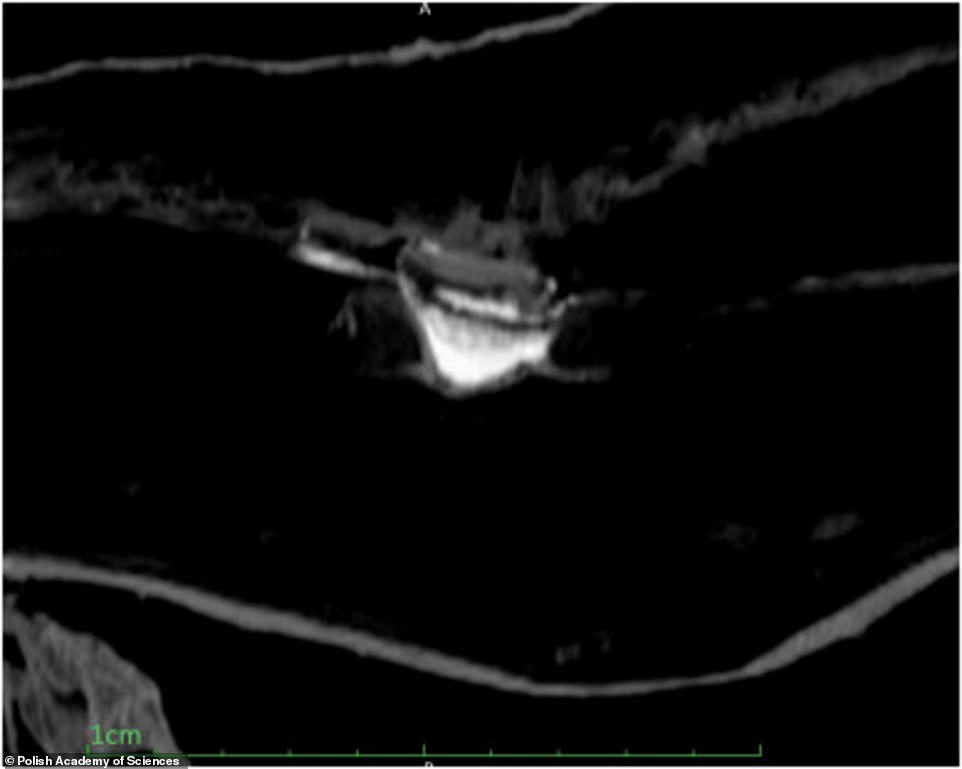

Ученые использовали множество различных фильтров, чтобы изучить мумию сканером, не дотрагиваясь до нее. Было установлено, что женщина находилась примерно на 26-28 неделе беременности, плод находится в положении эмбриона, пол ребенка определить не удалось.